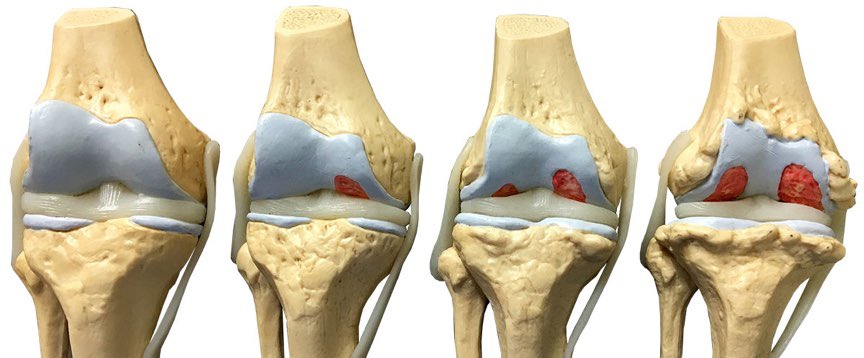

يعتبر مرض احتكاك المفاصل من الامراض الشائعة مع تقدم السن، ومفصل الركبة من اكثر المفاصل عرضة للاحتكاك

فالاحتكاك عبارة عن تآكل غضاريف المبطنة للركبة، مما يؤدي للالتهابات والم مزمن وتّكون نتؤات عظمية وتضيق في المفصل

حيث لايوجد حل طبي لإعادة تكون هذه الغضاريف